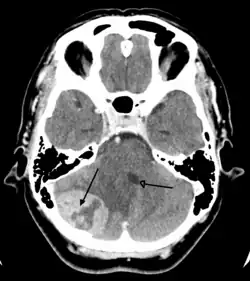

Imaging

Medical imaging plays a central role in the diagnosis of brain tumors. Early imaging methods – invasive and sometimes dangerous – such as pneumoencephalography and cerebral angiography have been replaced by non-invasive, high-resolution techniques, especially magnetic resonance imaging (MRI) and computed tomography (CT) scans.[42] MRI with contrast enhancement is the preferred imaging test in the diagnosis of brain tumors.[24][43] Glioblastomas usually enhance with contrast on T1 MRI weighted MRI imaging, and on T2 with FLAIR imaging showing hyperintense cerebral edema.[24] Low grade gliomas are usually hypointense on T1 MRI, and hyperintense with T2 with FLAIR MRI. Meningiomas are usually homogenously enhanced with dural thickening on MRI.[24]